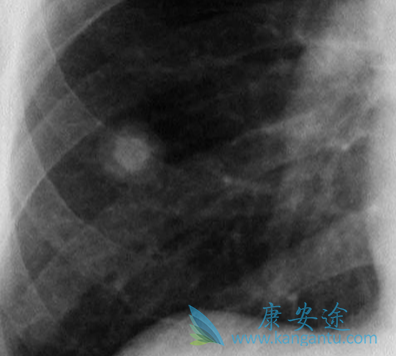

一般肺癌发现都比较晚,很多病人和家属都不敢信息,因为好好的一个人就被确诊为肺癌晚期了,实在难以接受,今天小编给大家讲下肺癌晚期症状,以及治疗。肺癌疼痛,声音嘶哑,面、颈部水肿,气促、胸腔积液等都是常见的肺癌晚期症状。

肺癌能治好吗?就晚期肺癌的治疗方法而言,手术切除的可能性很低,临床上晚期肺癌的主要治疗方法有放疗、化疗、中医药治疗。虽经手术但肿块无法切除,虽然经过放化疗但肿块未完全消失,或转移灶明显无法再进行手术、放化疗。而服中药数年,肿块变化不大,或缩小、或稍有增大,但生存期延长、生存质量提高,这也是“带癌生存”的最大特点。